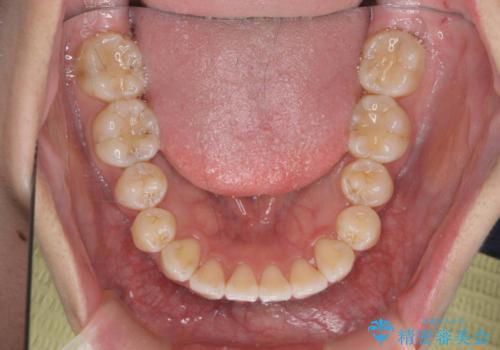

- 前歯の噛み合わせの開きの改善を求めて来院されました。

奥歯はほとんど動かさず(奥歯の噛み合わせはほとんど変えず)前歯のIPR矯正でガタつき前突感(出っ歯感)の改善を計画します。

ほとんど前歯のみの矯正治療であることからトータル14枚のマウスピースで並べるインビザラインライトによる治療を行います。

インビザラインライトは全14枚のマウスピースで行う軽度なガタつきなどの改善を目的とする矯正治療です。(約3.5ヶ月)

今回の治療では追加でマウスピース治療を行なったため、半年弱の治療期間となりました。